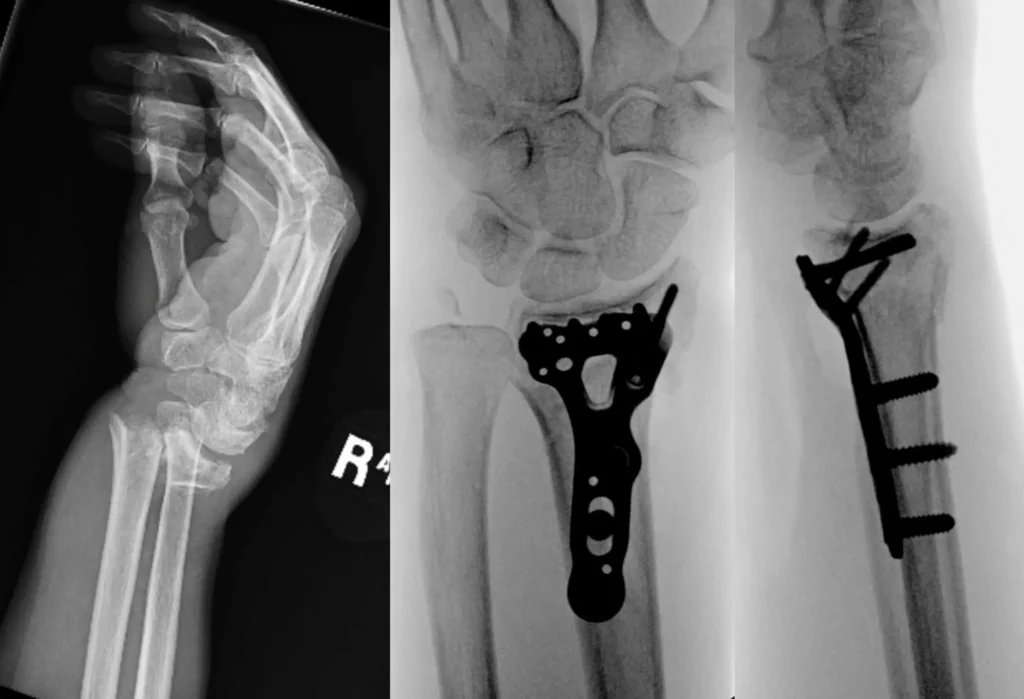

Treatment Imaging

Fracture Care